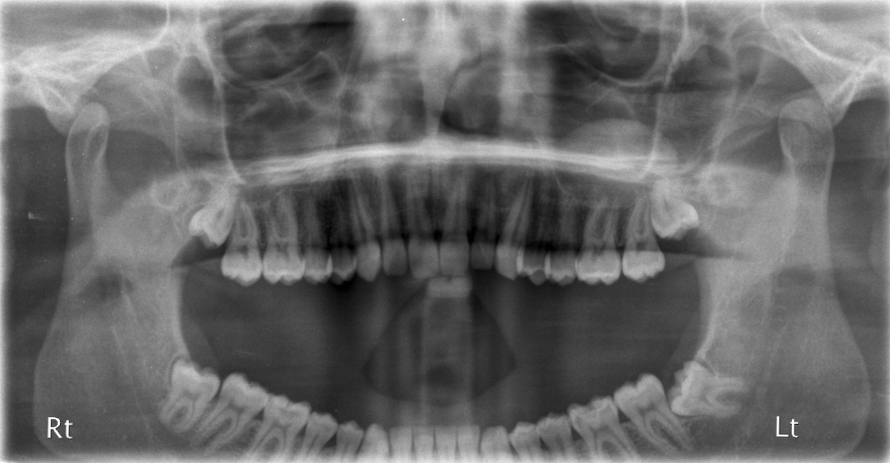

Mouth-Sinus Communications.

Mouth-Sinus Communications. Upper molar and premolar teeth often have their roots in close proximity to the sinus. In removing these teeth, there is a chance that a ‘hole’ can be made between the mouth & the sinus (this is sometimes not evident at the time of operation but may develop several weeks afterwards). If this ’hole’ persists or is left un-repaired, every time you drink, fluid can come out of the nose and you may develop a marked sinusitis. This ‘hole’ if small enough, can spontaneously close. It can be assisted in this by ‘cover plates’ that prevents food & fluids going into the sinus allowing the hole to close naturally. However, ‘holes’ above a certain size need to be surgically closed.

Fractured Tuberosity.

Fractured Tuberosity. The upper molars can, from time to time, be fused with the bone around them so that in removing the molar tooth, the bony socket within which the tooth sits (tuberosity) comes with it. This can make the mouth-sinus communication larger and sometimes, the adjacent teeth and their bony sockets comes attached with the extracted tooth.